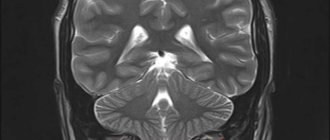

Определение Синдром Арнольда Киари I типа состоит в опущении нижней части мозжечка – миндалин